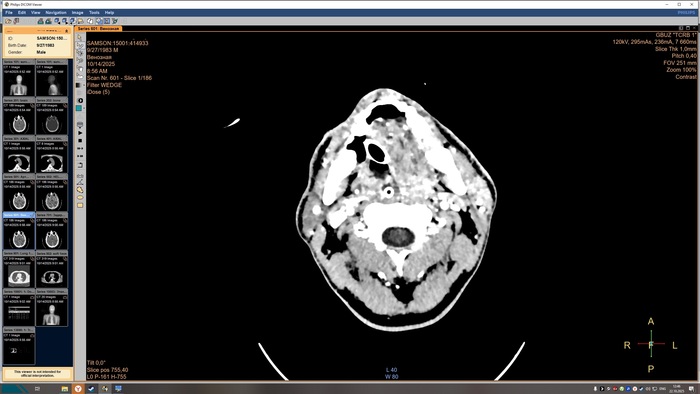

Описание КТ прикрепляю, а снимки будут в конце поста, по-другому у меня не получилось.

На топограмме, серии аксиальных срезов и реконструкций получены изображения суб- и

супратенториальных структур головного мозга от большого затылочного отверстия до крыши

черепа в нативном виде и в/в контрастированием. Определяются: справа четко

идентифицируемые внутричерепные интрапаренхиматозные гиперденсные неоднородные

очаги, копящее контрастное вещество, плотностью до 51-55ед.Х., размером: в проекции

лучистого венца 8х8х9 мм, в проекции продолговатого мозга 21х26х19 мм, Срединные

структуры мозга не смещены. Боковые желудочки: правый до 10,2 мм, левый до 12,9 мм,

третий-2,6 мм, четвёртый-13,8 мм. Селлярная и хиазмальная области без видимых

патологических изменений. Цистерны основания мозга, конвекситальные ликворные

пространства и борозды полушарий большого мозга сужены. Оболочки мозга без

особенностей. Миндалины мозжечка расположены соответственно возрасту. Дополнительных

образований и жидкостных скоплений в воздухоносных полостях височных костей с обеих

сторон, полости носа и его придаточных пазух не выявлено. Содержимое глазниц

визуализируется без особенностей. Признаков остеолитического, -пластического процессов,

аномалий развития и/или травматических повреждений костей черепа исследованного уровня

не выявлено. На прямой топограмме, серии аксиальных срезов и реконструкций получены

Снимки КТ